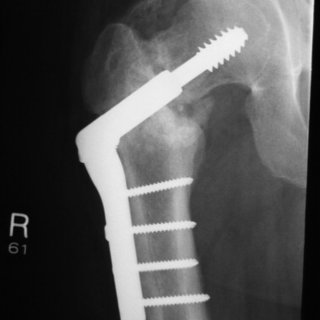

What internal fixation method has been used to internal fix this hip?

Dynamic hip screw